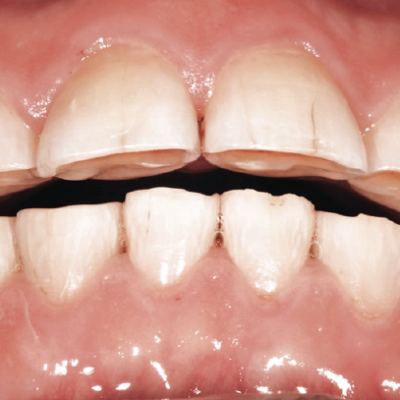

What is tooth wear?

Tooth wear also called 'Occlusal Disease' is one of the most prevalent dental problems of the modern age. This is defined as the loss of dental hard tissue(mainly enamel) caused by factors other than tooth decay or trauma. As we age the amount of wear increases on our teeth and thus...

Treatment for tooth wear

Due to the effect of tooth wear, some degree of enamel loss is always present. We follow the concept of minimally invasive treatment which means we preserve as much of your tooth structure as possible and aim to just adding 'enamel' back to the tooth. In essence you have...